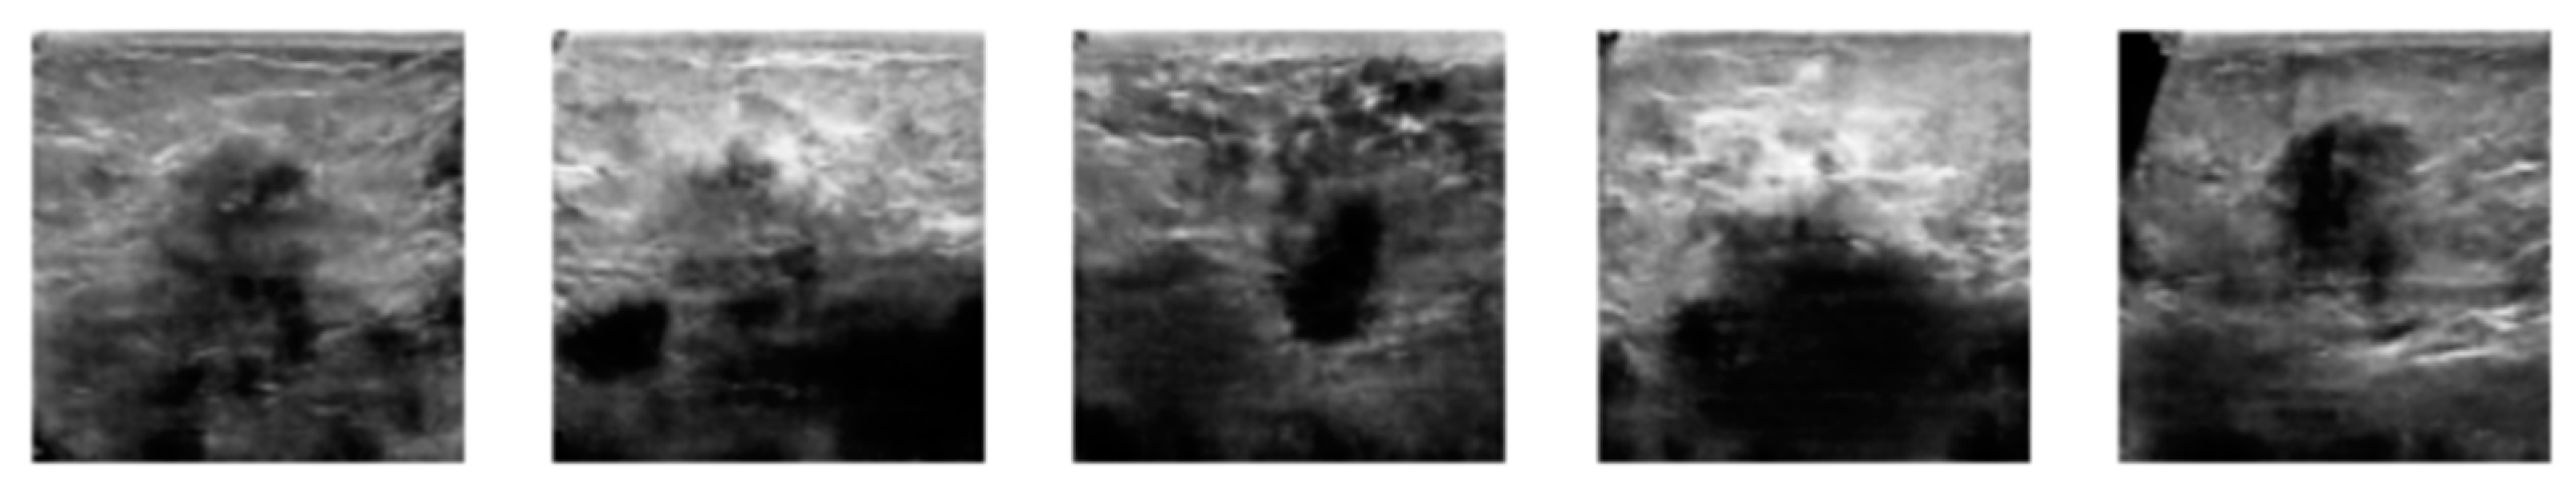

3.2. Image Synthetic Augmented by WGAN